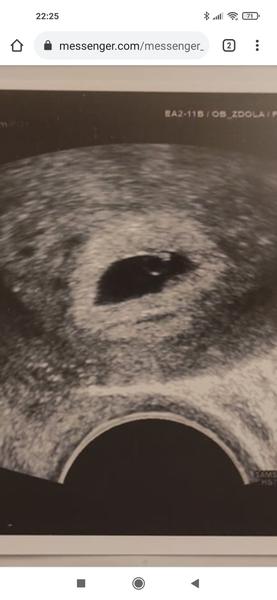

Miminko 5. - 6.tt. Není moc malinké?

Miminko tam zatím není 😀 je tam tečka, zárodek. V dutince. Naprosto správný nález na 5-6tt. Klid.

@ls1 úplně normální, odpovídá týdnu těhotenství.